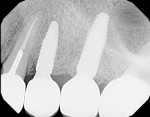

The patient's chief concern was a failing bridge in the upper left posterior sextant. Tooth No. 11 was severely decayed, necessitating endodontic treatment, post, and crown to salvage. Tooth No. 13 had a vertical fracture, which left it with a hopeless prognosis (Figure 1). The treatment plan included the extraction of tooth No. 13 and placement of dental implants in position Nos. 12 and 13. Traditionally, the clinician would have considered a two-stage approach for tooth No. 13, which typically would require 3 to 6 months of hard- and soft-tissue maturation prior to implant placement.

Healing was uneventful. A full 6 months was allowed for hard- and soft-tissue maturation (Figure 10). An implant stability quotient (ISQ) value (Osstell, osstell.com) of 68 for the grafted site was noted at stage II, which is very good for type IV bone (Figure 11). The final restorations were fabricated, consisting of four individual units for teeth Nos. 11 through 14 (Figure 12). The periapical x-ray taken shortly after delivery of the prosthetics depicted osseointegrated implants in position Nos. 12 and 13 (Figure 13). The CBCT revealed that the implant in position No. 13 was well positioned and demonstrated complete regeneration of the buccal plate (Figure 14).